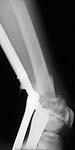

A male 22 years old referred to us from another town. More than 1 month ago (Apr 20) he was injured in a car accident. Among other injuries there was an open distal femoral fracture which hasn't been surgically fixed yet, only traction applied. There are scabs at anterolateral surface over the fracture site even today. No signs of infection though. Fracture mobility is aready limited. What treatment options do you consider for the case? THX in advance.

22 year old 4 weeks after distal femur fracture. Very comminuted metaphysis with some displacement. Intra-articular with some displacement. At least 2 condylar fragments. Most of the comminution appears metaphyseal. Probably grade 2 open soft tissue injury.